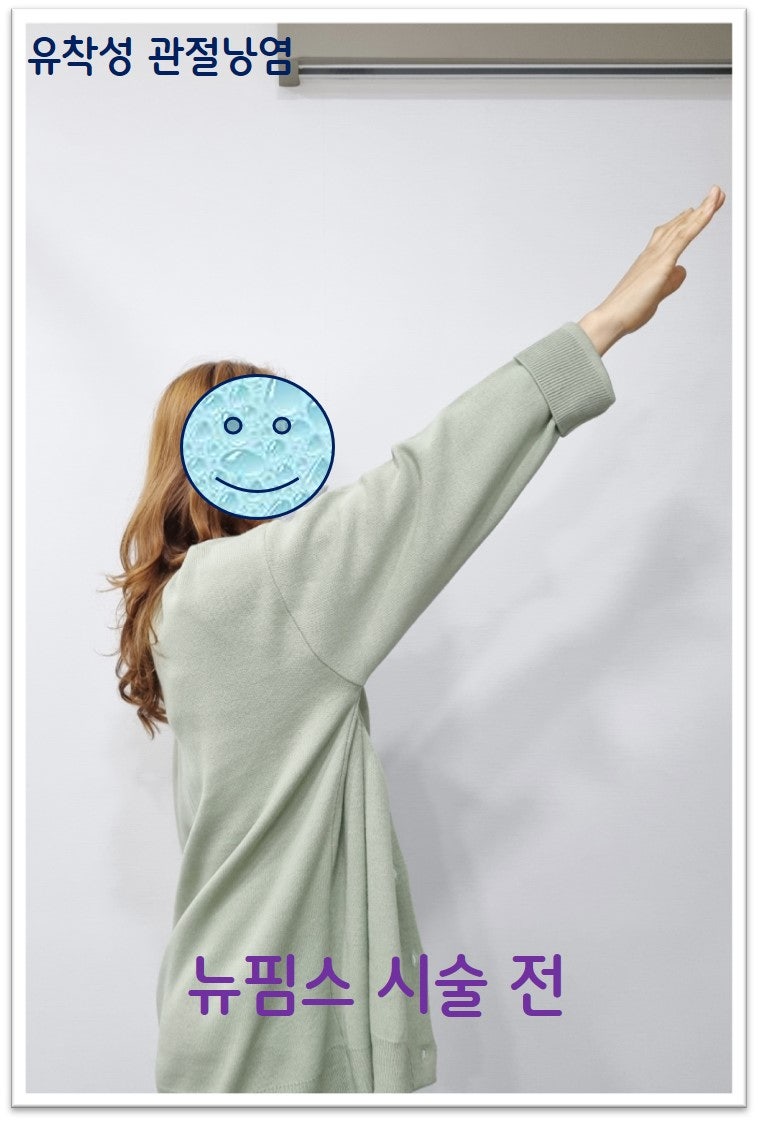

안녕하세요. 정형외과 전문의 이동규 입니다. 오늘은 오십견에 대한 뉴핌스 치료 사례에 대해 살펴보겠습니다. 48세 여자 환자로 1년간 어깨 통증 및 가동범위 제한이 있었습니다. 타병원에서 수차례의 주사치료, 충격파 치료, 도수치료를 받아왔지만 증상의 호전이 되지 않아 본원으로 내원하게 되었습니다. 이학적 검사상 가동범위 제한이 있었으며 약간의 empty can test 양성 소견이 보였습니다.

오랜기간 통증이 있어 왔으며 타병원에서 주사치료 및 도수치료를 수차례 했음에도 증상이 좋아지지 않아 뉴핌스 치료 (관절낭유착박리술) 를 시행하였습니다.